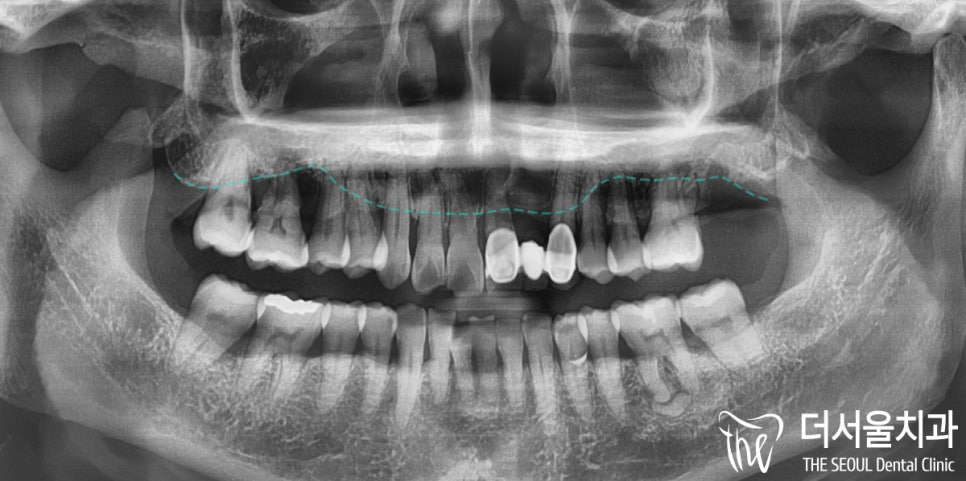

환자의 초진 사진입니다.

한눈에 봐도 구강 건강이 좋은 편은 아니였는데요.

파노라마 촬영을 통해 살펴보니

이미 광범위한 치조골 소실이 나타나 있었습니다.

제가 표시해둔 곳이 치조골 라인인데요.

이곳이 어느정도 튼튼하게 자리를 잡고 있어야

임플란트도 튼튼하게 심을 수 있습니다.

그러나 터무니 없이 모자란 양이 관찰되며

심지어는 상악동과의 거리도 근접해서

상악동거상술을 동반해야겠네요..